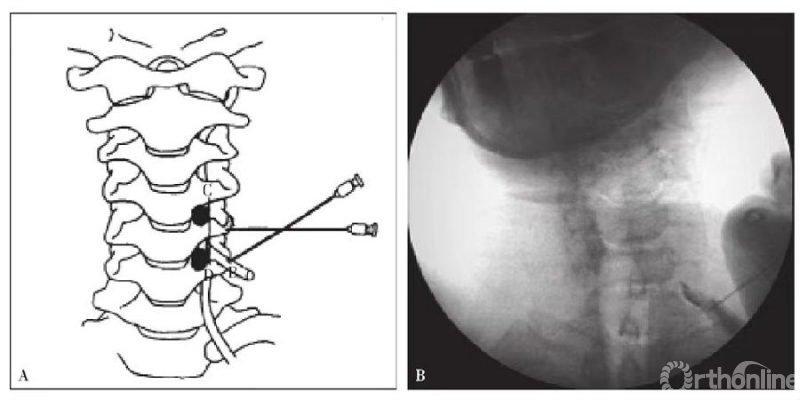

(3)术者置入穿刺针后,首先,到达目的神经根头侧颈椎的横突前结节A点,然后稍微回退,躲开前结节再向内、尾侧刺入,到达B点,目的神经沟的管状骨性结构。穿刺到目的神经根即可诱发相应的放射痛(图4A);

(4)注入造影剂1~2ml(通常为水溶性,如碘海醇),X线透视,观察神经根显影(图4B);

(5)注入0.5~1ml 1%利多卡因,判断根性疼痛症状缓解情况。如果是治疗目的,通常在利多卡因基础上,加用皮质激素(如1ml复方倍他米松注射液)阻滞治疗。影像解读和阻滞效果判断与腰椎类似。

图4 颈椎C6神经根选择性穿刺造影 A.穿刺示意图;B.C6神经根造影图说明:由于颈椎C1和C2解剖特殊,本操作步骤仅适合C3~7神经受压引起的神经根性疼痛的定位诊断和神经阻滞治疗。